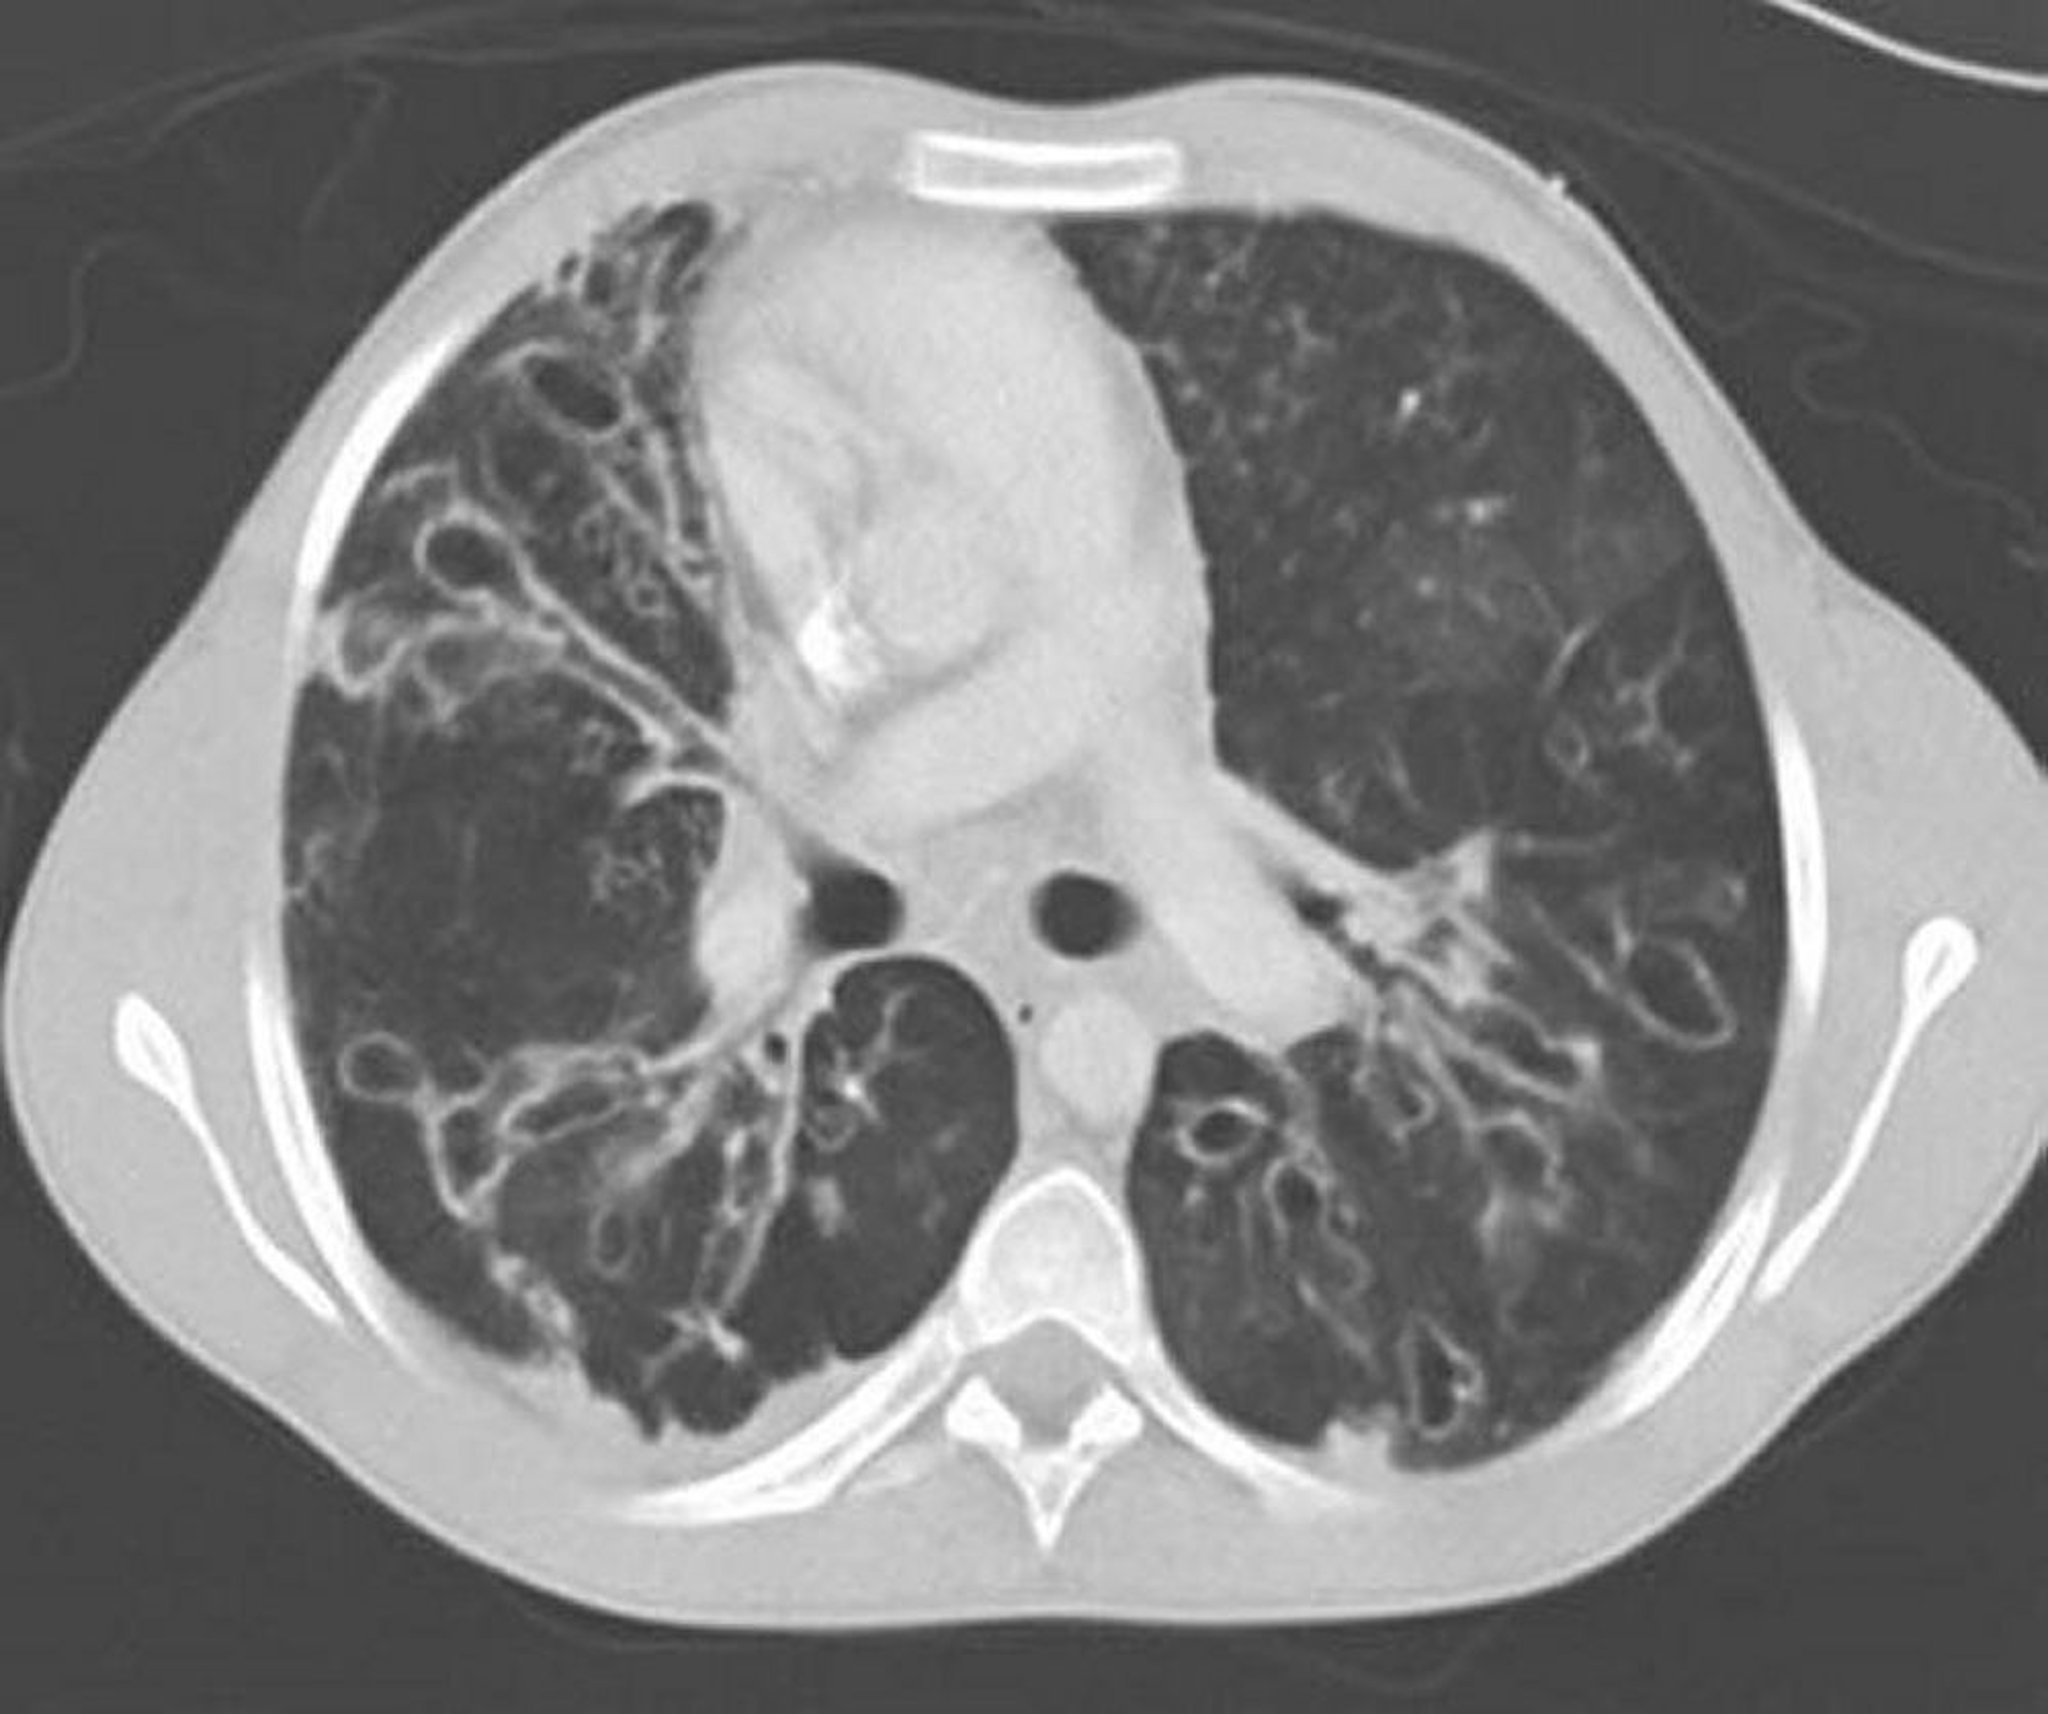

アレルギー性気管支肺アスペルギルス症(気管支拡張症)

胸部造影CTでは中肺野に大きく拡張した気道および嚢胞性変化を伴う重症の気管支拡張がみられる。気道の拡張は,隣接血管に対する気道の比が1を超えることを特徴とする。